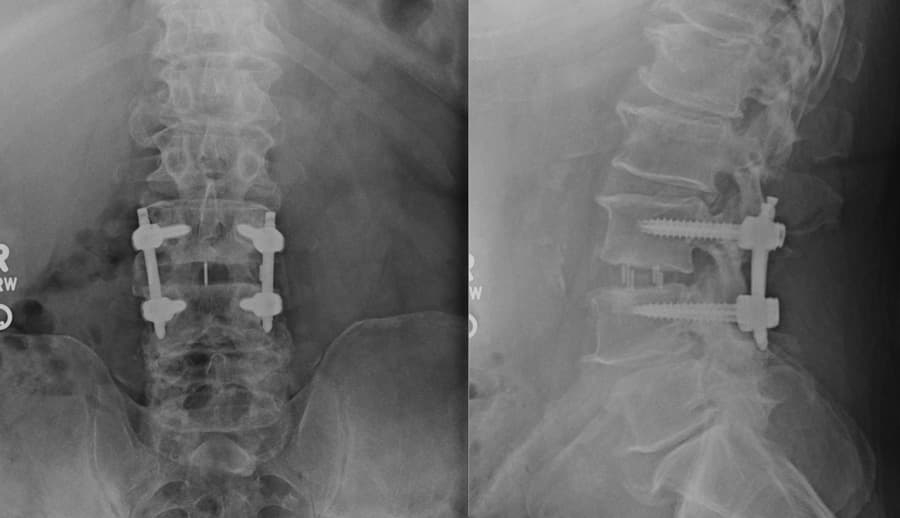

Lateral Lumbar Interbody Fusion

Lateral lumbar interbody fusion (LLIF) is a minimally invasive surgical procedure that addresses conditions in the lower back by approaching the spine from the side (lateral). This technique, sometimes referred to as XLIF or DLIF, is used to treat conditions like degenerative disc disease, spinal stenosis, and spondylolisthesis.

During an LLIF, the patient is positioned on the surgical table, and the surgeon makes a small incision in the side of the abdomen, avoiding the large muscles of the back. The abdominal muscles and internal organs are carefully moved out of the way to access the intervertebral disc from the side of the spine. The damaged disc is removed, and a metal spacer is inserted into the disc space. This restores the height between the vertebrae, decompressing the nerves and promoting fusion. Because the lateral approach avoids major back muscles, it often results in less post-operative pain, reduced blood loss, and a shorter recovery time compared to traditional fusion surgeries. Additionally, the natural curve of the spine and disc height can be better restored to their native condition.